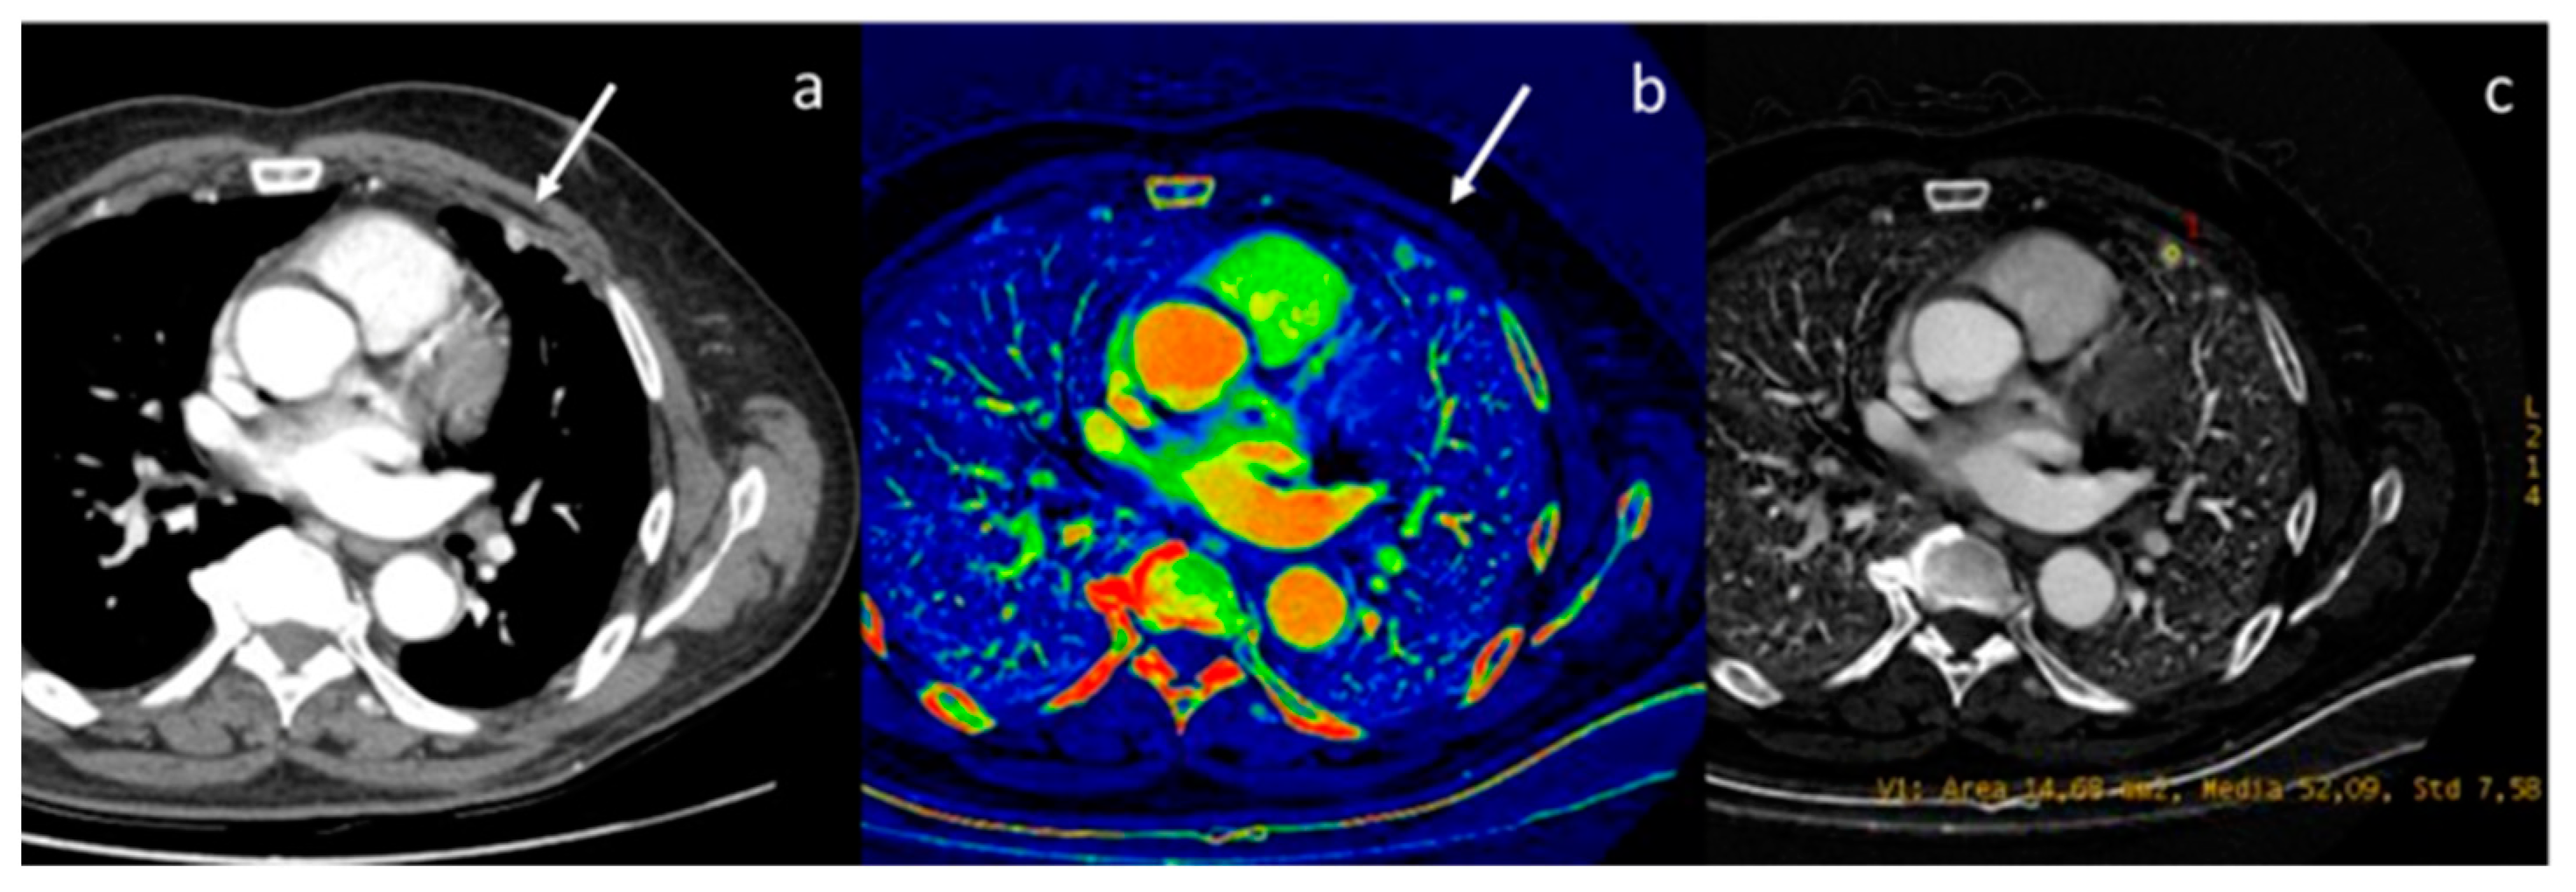

- Zhang, X.; Zheng, C.; Yang, Z.; Cheng, Z.; Deng, H.; Chen, M.; Duan, X.; Mao, J.; Shen, J. Axillary Sentinel Lymph Nodes in Breast Cancer: Quantitative Evaluation at Dual-Energy CT. Radiology 2018, 289, 337–346. [Google Scholar] [CrossRef] [PubMed]

- Terada, K.; Kawashima, H.; Yoneda, N.; Toshima, F.; Hirata, M.; Kobayashi, S.; Gabata, T. Predicting axillary lymph node metastasis in breast cancer using the similarity of quantitative dual-energy CT parameters between the primary lesion and axillary lymph node. Jpn. J. Radiol. 2022, 40, 1272–1281. [Google Scholar] [CrossRef] [PubMed]

| Zhang et al. [60] Prospective study | China | To evaluate the diagnostic performance of quantitative parameters derived from DECT for the preoperative diagnosis of metastatic sentinel lymph nodes, in participants with breast cancer | 193 | Discovery CT 750 HD, GE Healthcare No C.I. | The accuracy of the venous phase slope HU for detecting metastatic sentinel lymph nodes was 90.5% on a per-lymph node basis and 87.0% on a per-patient basis. The accuracy and specificity at venous phase slope HU were higher than their counterparts in the morphologic parameters (p < 0.001). |

| Terada et al. [61] Retrospective study | Japan | To evaluate the similarity of quantitative DECT parameters between the primary breast cancer lesion and axillary LN for predicting LN metastasis. | 137 | Revolution CT; GE Healthcare, Chicago, IL, USA No C.I. | The quantitative DECT parameters, including the slope HU, IC, and attenuation values at 40 keV and 70 keV, were useful for predicting LN metastasis, as previously reported. However, these DECT parameters may be influenced by differences in the CT scanner, scanning protocols, and injection protocols of the contrast medium. |